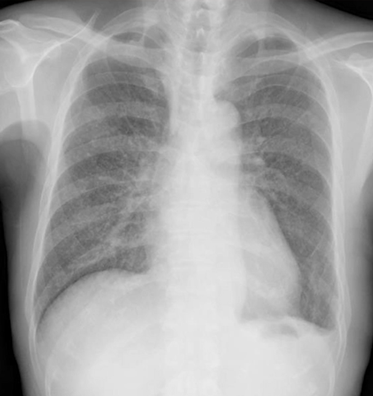

粟粒結核の胸部レントゲン(X-p)写真

微熱が続き胸部レントゲン写真を撮ることがあります。粟粒結核をX-pで見抜くコツとすると、粟粒結核のレントゲンでは、両方の肺全体にびまん性(広がって)に散らばった、数ミリ以下の粟粒状の小さな影が特徴的です。進行するとこれらの影が大きくなったり、癒合するので、そのような所見をとらえることもコツになります。

まさにこんな感じで、胸部レントゲンでは、びまん性の小粒状影が確認されます。CTにて精査です。